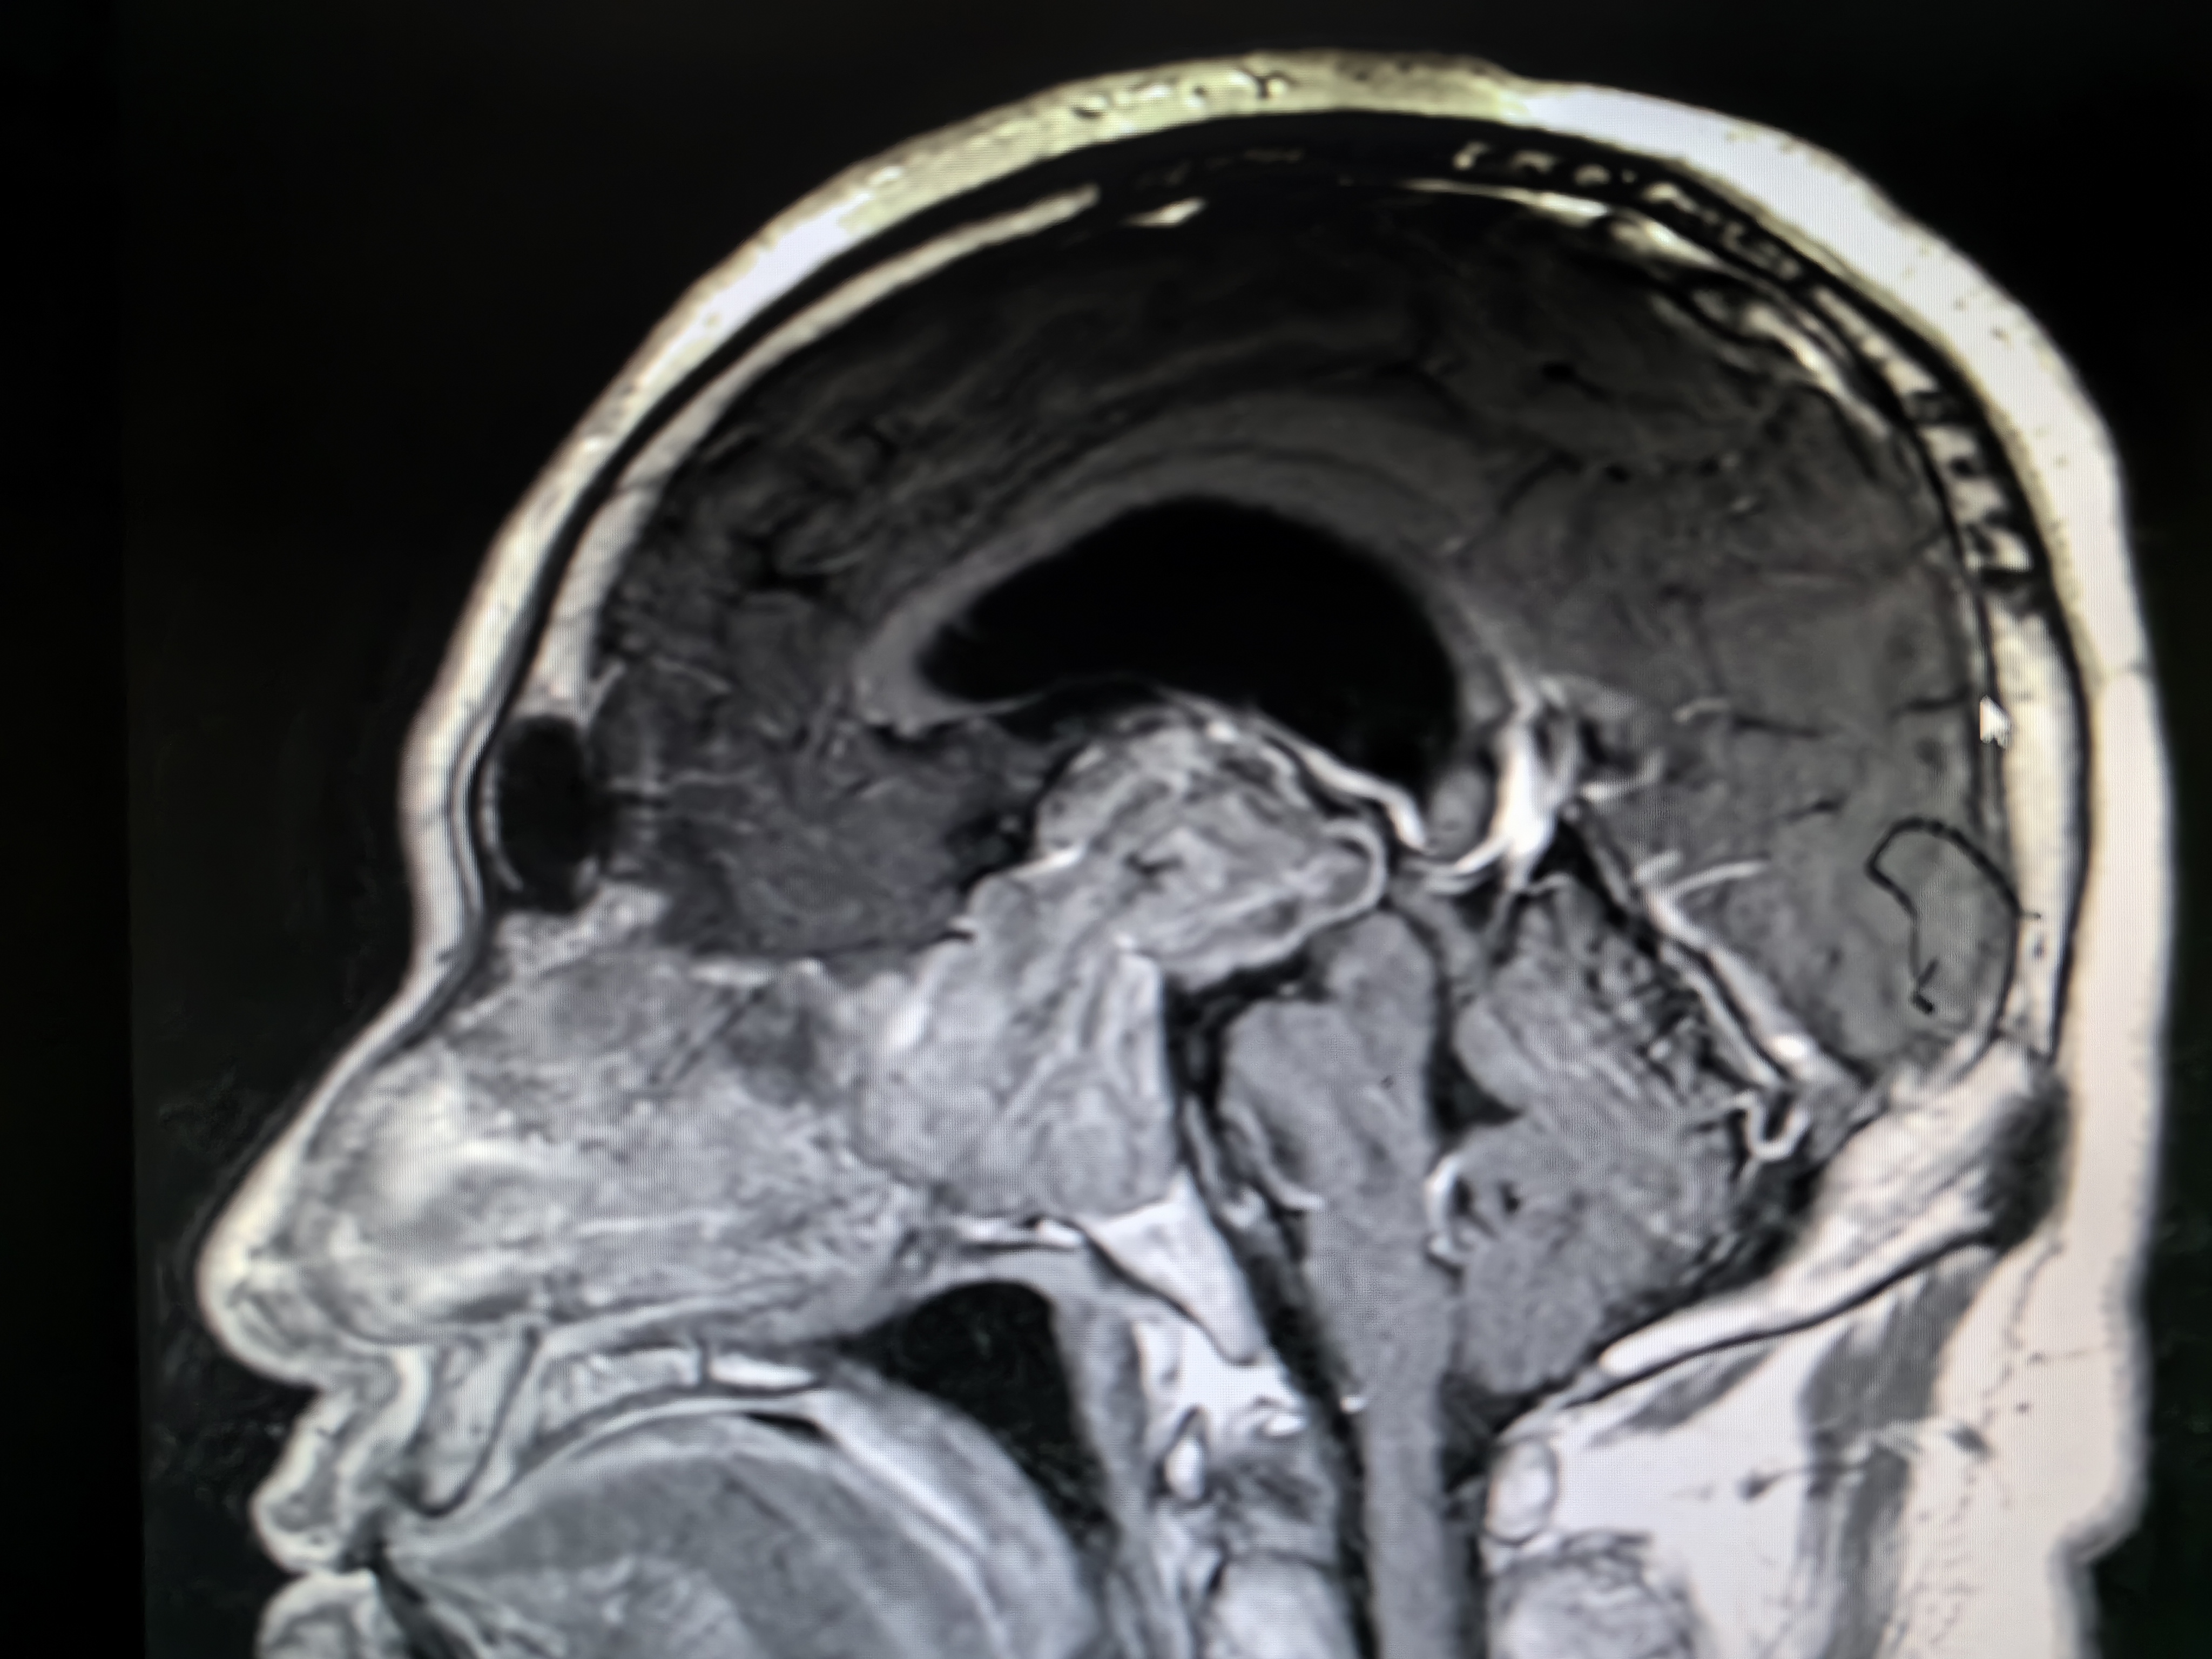

下面看一例病例:

扩大舌下神经管

术前磁共振,显示舌下神经管扩大

这个是手术过程,实践中感觉舌下神经管鞘瘤越小,越难暴露。

这例患者术前评估考虑肿瘤并没有浸透颅底硬脑膜,所以术中不必打开硬脑膜,减少了创伤,病人恢复很快。